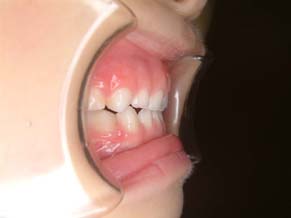

2か月後です。反対咬合は治っています。現在は正常な噛み合せになりました。

これからまだ永久歯に生え替わるので、注意深く定期的に観察していきます。生え替わった後に、また反対咬合になりこともあります。